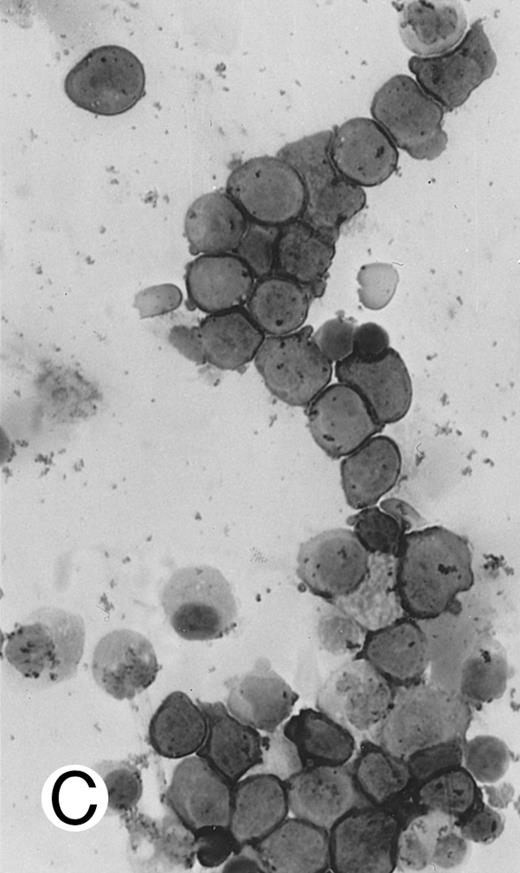

Immunocytochemical staining of aggressive NK cell leukemia/lymphoma (case no. 39), using the labeled avidin-biotin alkaline phosphatase system. The smears were prepared from mononuclear cells separated by density gradient centrifugation using Ficoll-Isopaque. (A) The cells are positive for CD2. (B) There is no reactivity for Leu4/CD3; the strongly stained small lymphocytes serve as internal positive controls. (C) The cells are reactive for CD56 (NKH1).

The immunophenotype as analyzed on fresh/frozen tissues was CD2+ CD3/Leu4− CD4− CD5− CD7− CD8− CD16− CD56+ CD57− (Fig 7). In paraffin sections, the neoplastic cells showed reactivity with the polyclonal CD3ε antibody. In all cases, nuclear labeling for EBER was observed in the majority of neoplastic cells.